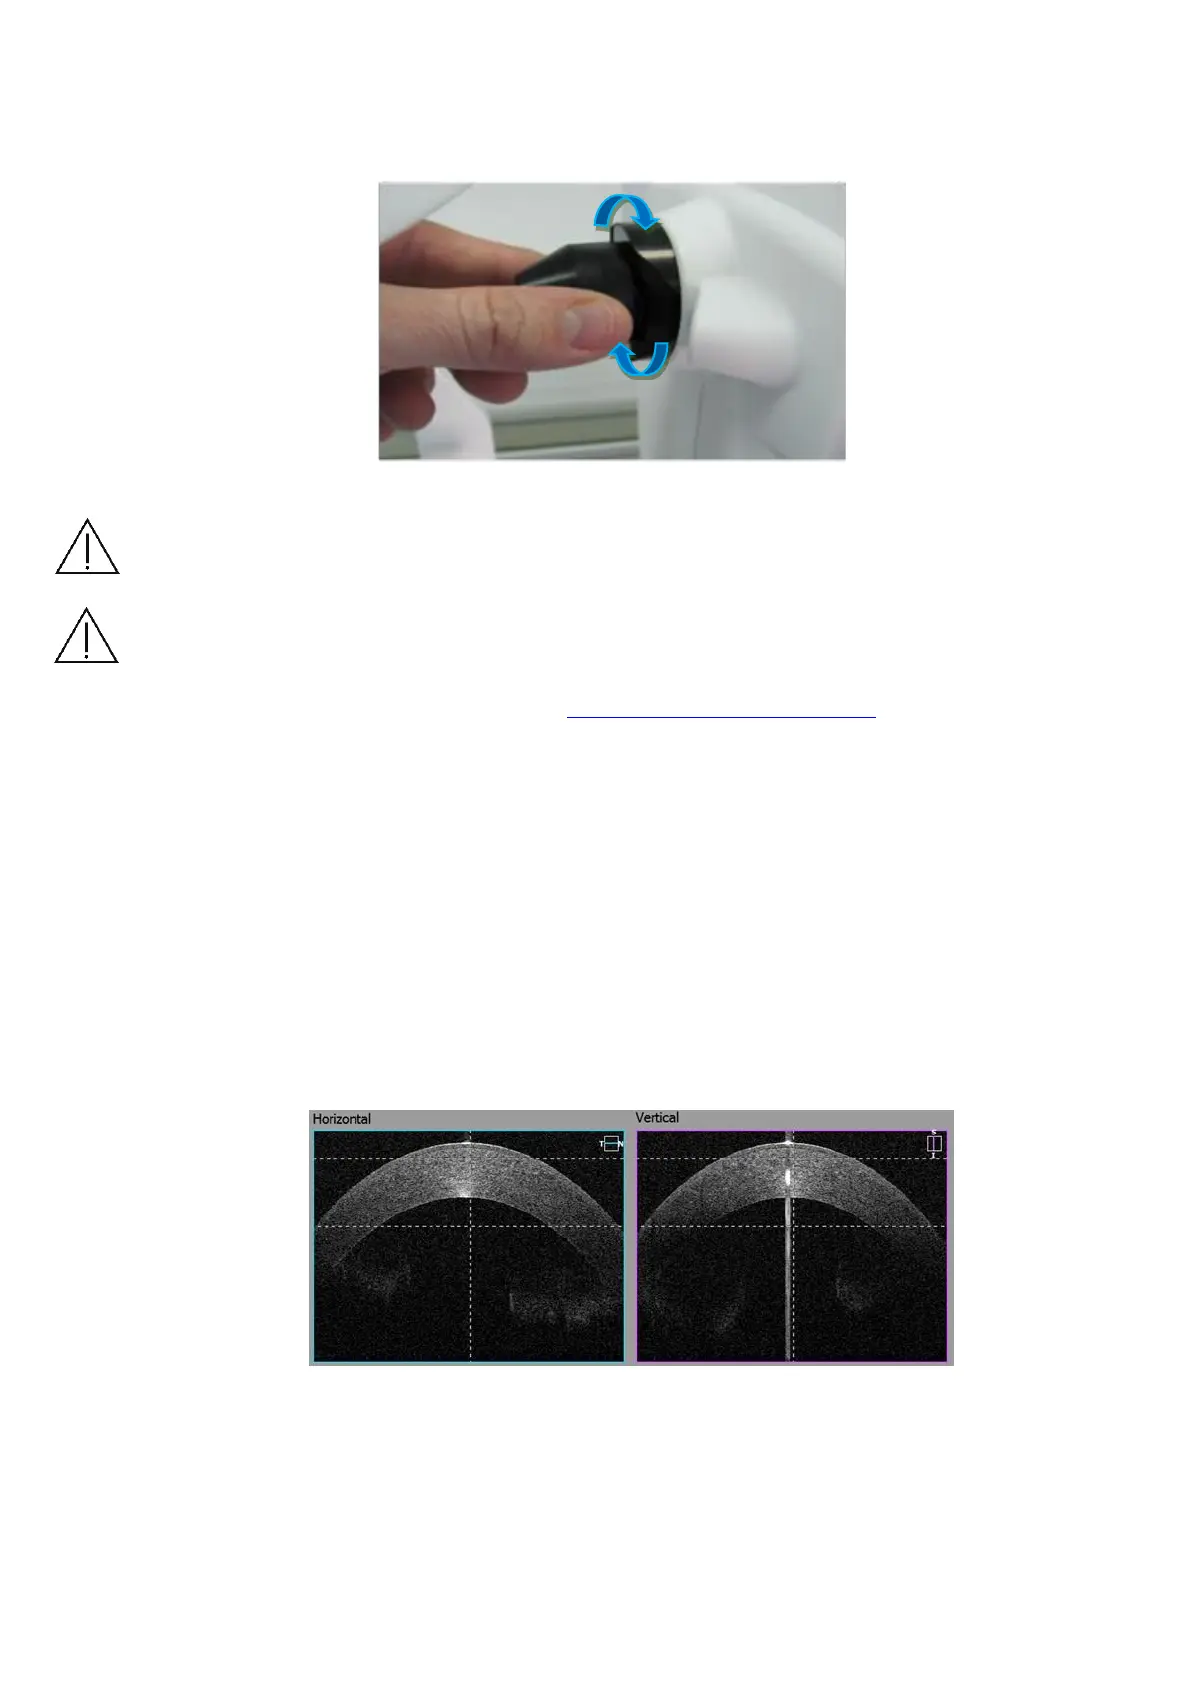

Wide Cornea scan For pachymetry map use Anterior Radial scan. Locate the

cornea in between two dashed lines to get the best cornea images. Use center

reflex from cornea to locate the scan in the middle of scanned window. Use vertical

dashed lines as reference.

Figure 50. Wide Cornea scan proper alignment